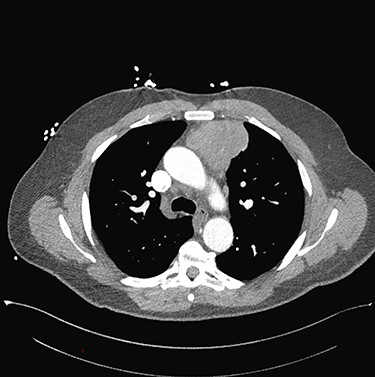

Sixty-three-year-old male was with the history of diabetes and hypertension who presented with 2 days of new onset, intermittent and non-pleuritic left-sided chest pain, with a few months of new onset exertional dyspnea. Chest X-ray showed a convex shaped mass at the left hilum. Chest CT angiography revealed a 5.6 × 7.1 × 5.4 cm hypodense mass in the anterior mediastinum involving the adjacent anterior medial left upper lobe, and adjacent mildly enlarged aorticopulmonary window lymph nodes (Fig. 1). PET scan demonstrated a hypermetabolic anterior mediastinal mass adjacent to medial left upper lobe highly suggestive of malignancy (Fig. 2). Ultrasound-guided core needle biopsy showed nests of small cells with peripheral palisading and focal abrupt transition to squamous cell, consistent with basaloid carcinoma of thymic gland. Immunostainings of the tumor cells were positive for cytokeratin AE1/AE3, cytokeratin CK904, p63 and p40.

Pre-operative PET scan demonstrating a hypermetabolic anterior mediastinal mass.